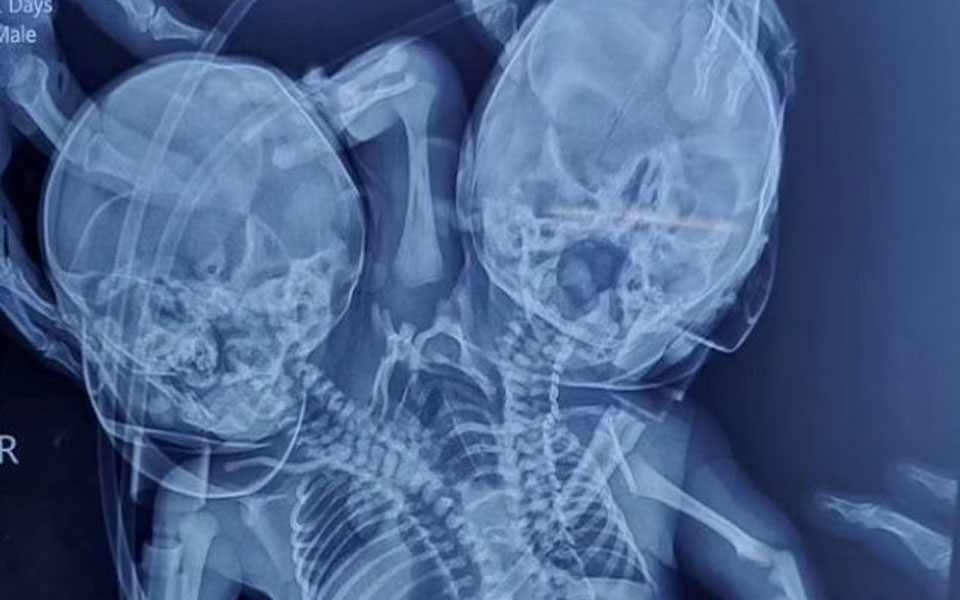

Ένα ασυνήθιστο γεγονός συνέβη στην Ινδία όπου ένα μωρό γεννήθηκε με δύο κεφάλια, τρία χέρια και δύο καρδιές. Ξένα μέσα αναφέρουν ότι οι γονείς της Shaheen Khan και ο σύζυγός της, Sohail, περίμεναν πλήρως σχηματισμένα δίδυμα, αλλά σοκαρίστηκαν όταν γέννησε ένα δικέφαλο μωρό στις 28 Μαρτίου στο Ratlan, στην ινδική πολιτεία Madhya Pradesh.

Όπως μετέδωσε η ΕΡΤ, αυτή η διαταραχή είναι γνωστή ως δικέφαλος parapagus dicefalik όπου δύο μωρά ενώνονται με έναν κορμό που συχνά οδηγεί σε θνησιγένεια. Όμως τα δίδυμα που συνδέονται από θαύμα έχουν επιζήσει μέχρι στιγμής και έχουν εισαχθεί σε νοσοκομείο στην κοντινή πόλη Indore για να παρακολουθούνται από γιατρούς.

«Τέτοιου είδους περιστατικά είναι σπάνια και η κατάσταση των μωρών παραμένει επικίνδυνη, ειδικά τις πρώτες μέρες», είπε ένας γιατρός.